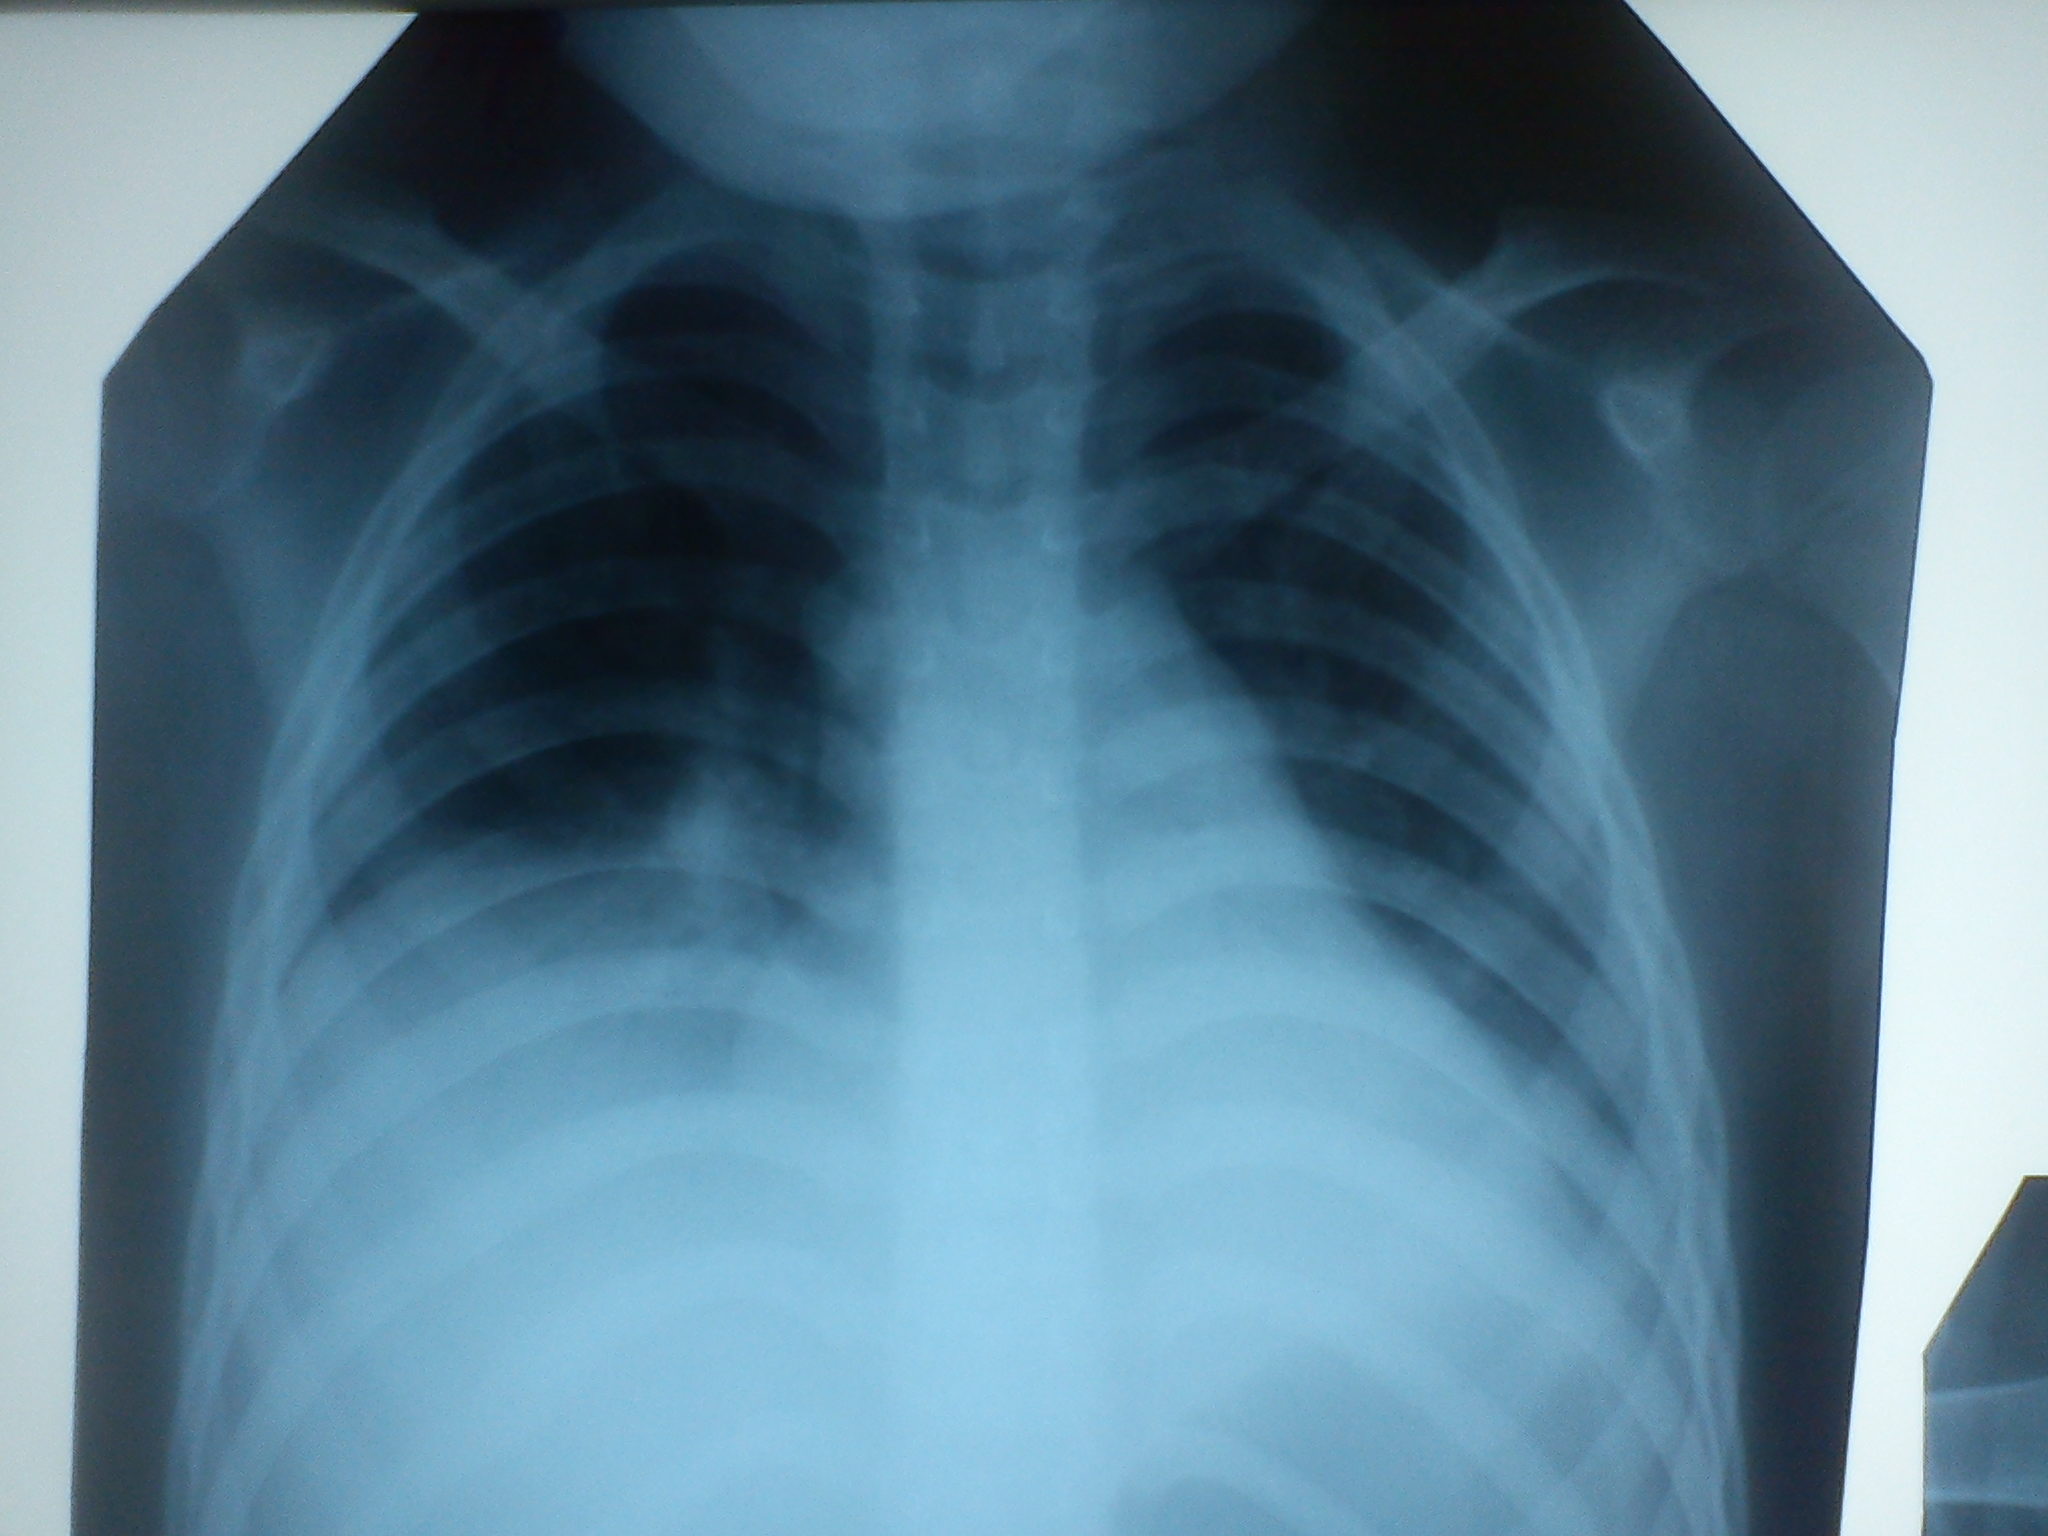

Добрый вечер. Помогите начинающему рентгенологу. Поступил ребёнок 10 лет с 2-х сторонней пневмонией. На снимке от 31.05. в нижней доли правого легкого кольцевидная тень. Что это? Абсцесс?

На снимке от 31,05.14 кольцевидной тени нет. Скиалогический эффект. Перекрёст сосудов, рёбер создаёт такую неприятную картину. Настораживает отрицательная динамика на последней рентгенограмме от 4.06.(высокое стояние правого купола диафрагмы). Подозреваю осложнение - ателектаз. Как чувствует себя пациент? Делали ли боковую рентгенограмму?

Спасибо. Присмотрелась, а кольцевидная тень и правда скиалогия. Сегодня делали КТ, пневмония с 2-х сторон. Правый купол поднят за счёт высокого стояния печени. Ребёнок в отделении реанимации, тяжёлый, токсикоз с эксикозом.

Первые 2 снимка 29.05. Второй 31.05. Третий 4.06.